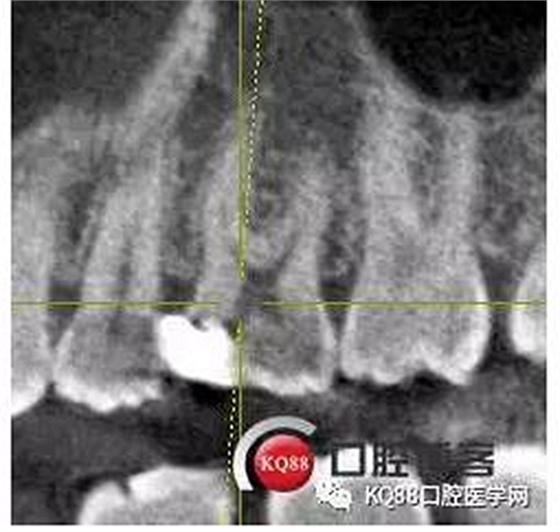

當(dāng)我第一次完成操作后,再次拍了一個(gè)插針片,發(fā)現(xiàn),距離根尖孔有1.5mm,書上說(shuō)的是2mm安全區(qū),可能如果隨意點(diǎn),就直接充填了,我想說(shuō)明的是,我們做根管,千萬(wàn)不要馬虎,不要湊合,一定嚴(yán)謹(jǐn)?shù)膽B(tài)度,于是我重新再回到C銼,再開始耐心的預(yù)備,完成之后,再拍攝了插針片。

此次明顯可以看見(jiàn)根尖分開了兩個(gè)根尖孔,根管治療永遠(yuǎn)就只是那一點(diǎn),如果都只是隨便做一下,我相信,沒(méi)有復(fù)雜的牙齒,根管治療都會(huì)很簡(jiǎn)單,態(tài)度決定一切,我不敢說(shuō)我做的會(huì)很好,但是我會(huì)靜下心來(lái),慢慢操作,這樣才能做得對(duì)的起自己和患者。于是根充完成,再次拍攝。